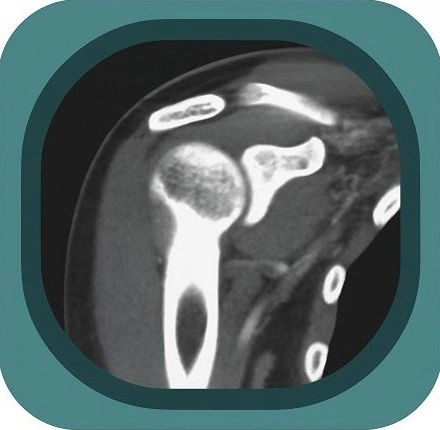

Explore full-body CT anatomy in 3 planes. Our high-resolution, carefully labelled images reveal micro-anatomy—ideal for radiologists, radiographers and surgeons.